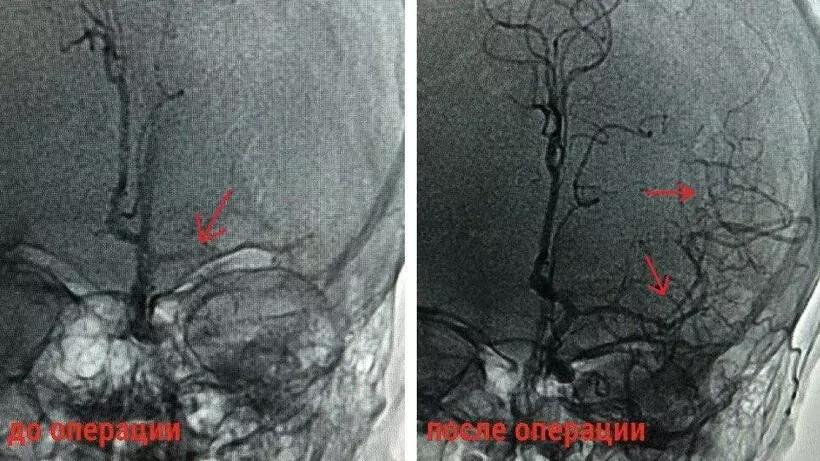

«Под рентген-контролем врачи провели тромбоэкстракцию – извлечение тромба из артерии головного мозга, что позволило специалистам восстановить кровоток. Операция прошла успешно», – рассказал заведующий отделением рентгенохирургических методов диагностики и лечения Леонид Гинзбург.